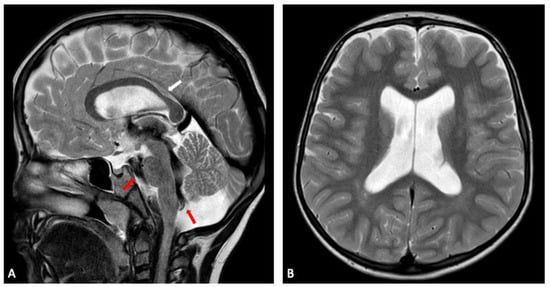

The youngest sibling showed the subtler clinical profile despite having structural abnormalities on imaging. MRI demonstrated a reduced right hippocampal volume with compensatory enlargement of the temporal horn, alongside thinning of the corpus callosum and mild pons hypoplasia. Motor and language skills developed more slowly than expected, but the overall course was steadier, and no seizures were reported. This combination of anatomical findings and comparatively mild clinical expression is in keeping with observations from larger cohorts, where even siblings carrying the same deletion can differ greatly in their developmental and behavioural outcomes.

Figure 6. Sibling 3. Brain MRI; axial (A) and coronal (B) T1-weighted gradient echo (GE) images showing a reduced-size right hippocampus (white arrows), compared to left normal hippocampus (yellow arrows). On the right side, the compensatory enlargement of the temporal horn of the lateral ventricle can also be noted (arrowhead).